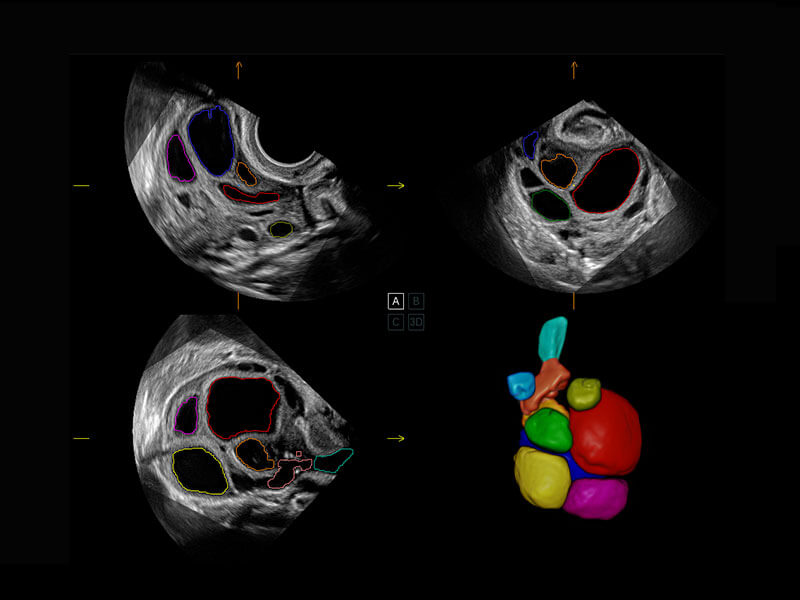

新生儿肝血管癌

新生儿脊髓圆锥

新生儿心脏